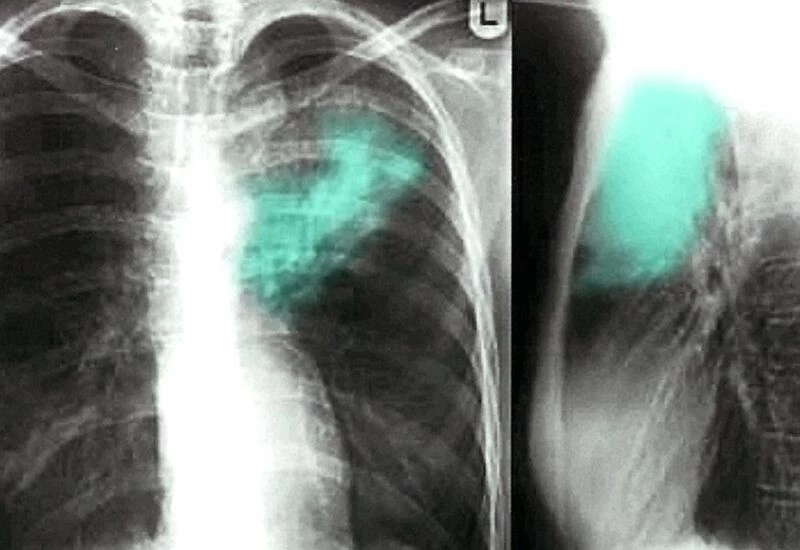

आखिर में डॉक्टरों ने महिला के फेफड़ों का एक्सरे किया। एक्सरे करने वाले डॉक्टरों ने फेफड़ों के ऊपरी दाहिनी ओर सूजन पाई। बारीकी से जांच करने पर पता चला कि यह सूजन फेफड़ों में जमे एक उल्टे बैग जैसी संरचना की वजह से है। इसी बैग की वजह से महिला को लगातार बुखार और खांसी बनी हुई थी।

इसके बाद डॉक्टरों ने तुरंत महिला के ऑपरेशन का फैसला किया और सर्जरी करके उस बैग नुमा चीज को बाहर निकाला। उस बैग को देखकर डॉक्टर हैरान रह गए। दरअसल वह बैग और कुछ नहीं एक कंडोम (Condom) था। जब डॉक्टरों ने महिला और उसके पति को आमने-सामने बिठाकर पूछताछ की तो महिला ने स्वीकार किया कि मुखमैथुन के दौरान उसने वह कंडोम निगल लिया था। कपल ने बताया कि शरीर में जाने के बाद कंडोम ढीला पड़ गया था। जिसकी वजह से महिला को खांसी और छींक शुरू हो गई।